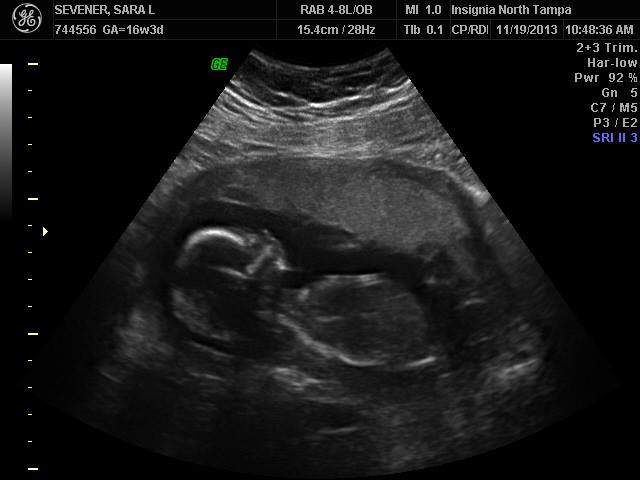

Saw our little guy wiggling around in there and verified that indeed he is, in fact, a guy! Which is probably in my best interests because I’m currently up to G in the boys section of the baby name book and I’d hate to have to start all over because I picked the wrong gender…